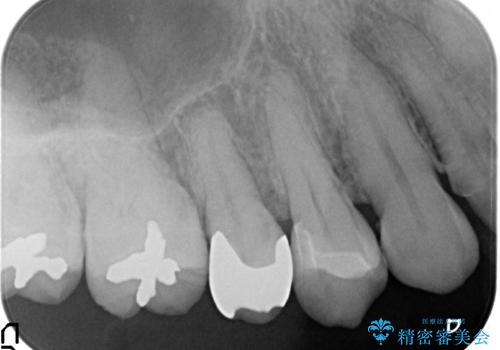

古い樹脂を除去後、セラミックインレーによる修復を行いました。

当院のセラミックインレーはemaxという強度と審美性に優れた材料を使用しています。

またプレス方式でインレーを製作しているため、削り出しで製作するCADCAMより優れた適合性も持ち合わせており、虫歯が再発しにくい修復物です。